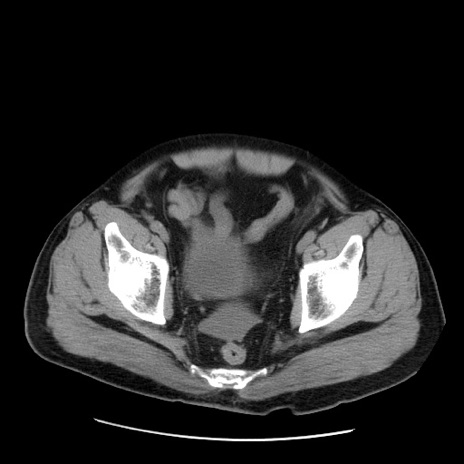

症例20(横断像)

矢状断像